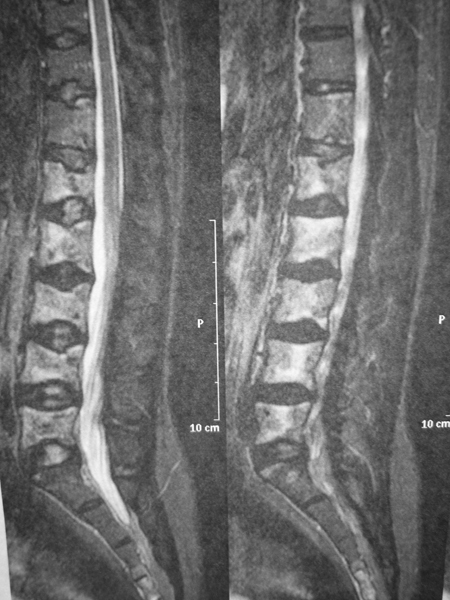

Quel est votre diagnostic ? Myélome. Rachis de la drépanocytose. Il s'agit bien d'un rachis de la drépanocytose (légendes : vertèbres biconcaves, hypersignal en T2). Ostéodystrophie rénale. Spondylarthropathie. Mastocytose. OK Valider mes réponses